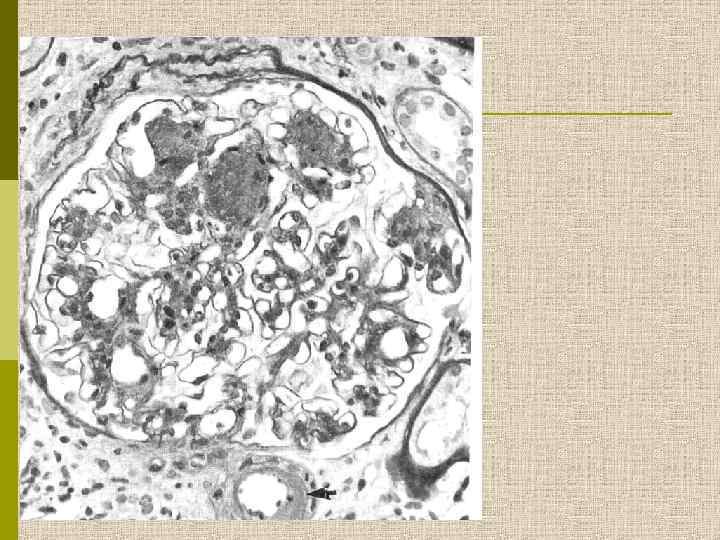

МОРФОЛОГИЧЕСКИЕ ИЗМЕНЕНИЯ ПРИ ДИАБЕТИЧЕСКОЙ НЕФРОПАТИИ Основные варианты - диабетический гломерулосклероз с узелками Kimmelstiel-Wilson - диффузный мезангиальный гломерулосклероз Характерные признаки Утолщение ГБМ; артериолярный гиалиноз; аневризматические капилляры; капсулярные капли; фибриновые шапочки; атрофия канальцев; инфильтрация, расширение и склероз интерстиция; линейные отложения иммуноглобулинов

Узелковый гломерулосклероз (болезнь Киммельстиля. Вильсона). Узелки pink гиалинового материала в области петель клубочковых капилляров – значительное уширение мезангиального матрикса в резельтате неэнзиматического гликозилирования протеинов.

PAS Узелковый гломерулосклероз (болезнь Киммельстиля-Вильсона) у больного с длительным течением сахарного диабета. Выраженное утолщением артериолы – типичный гилиновый артериолосклероз, наблюдаемый при сахарном диабете.